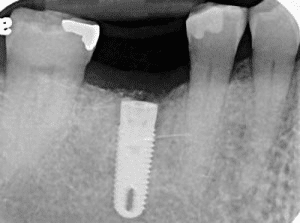

See the following examples of implants placed in the lower right first molar in two different patients.

Patient Experience: Case 1

An Ideally Placed Implant Using a Surgical Guide

Notice the difference in positioning between the guided placement and the freehand placement. The ideally placed implant in Case 1 is centered in the available bone space, allowing for optimal restoration design and long-term stability. This is the standard of care that Dr. Marlin follows for every implant placement.